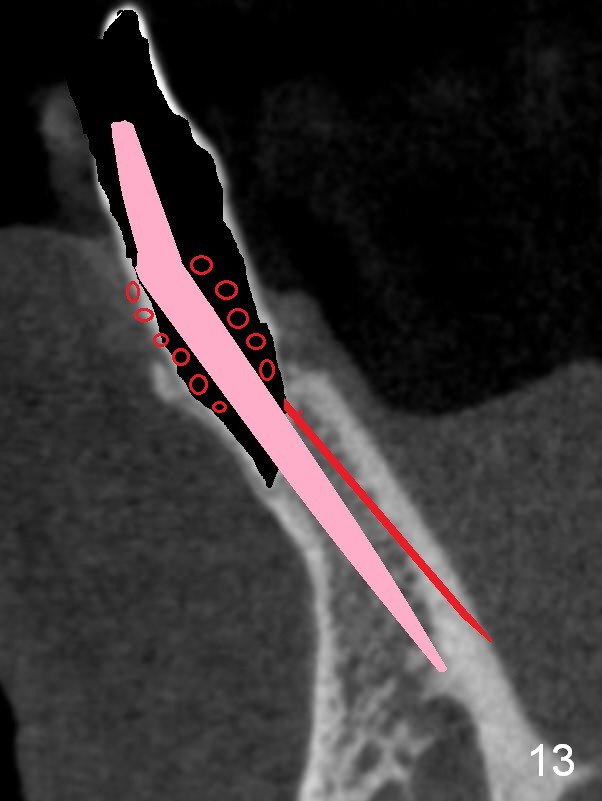

A 74-year-old man has several missing teeth (Fig.1).  His 1st goal is to replace the lower left lateral incisor (Fig.2).  The residual root has an apical lesion (Fig.3 *).  To describe intraop findings, a CT image of a different patient is used (Fig.4 coronal section; B: buccal; L: lingual).  After extraction, the buccal plate is found to be thin and low (Fig.5 arrowheads).  A 1.5 mm pilot drill (Fig.6 red line) is used to initiate osteotomy in the lingual plate of the socket.  Once the drill penetrates the lingual plate, the trajectory changes and the depth is 17 mm from the gingival margin (Fig.7).  A PA is taken (Fig.8); it appears that the osteotomy can be extended more apically.  When the pilot drill extends to 20 mm, there is sudden empty feeling.  The lingual plate has perforated (Fig.9).  A new osteotomy is established buccally (Fig.10 pink).  To avoid buccal plate perforation, especially in the buccal undercut area (>), the coronal end of the drill has to be tilted buccally (<--).  An angled abutment (3x20 mm, 15°) is placed (Fig.11,12).  The abutment is modified (Fig.13,14) to accommodate an immediate provisional (Fig.15,16 P).  Perio dressing is to be applied to prevent the bone graft from getting dislodged buccally (Fig.15).  The dressing is in place 7 days postop (Fig.17).